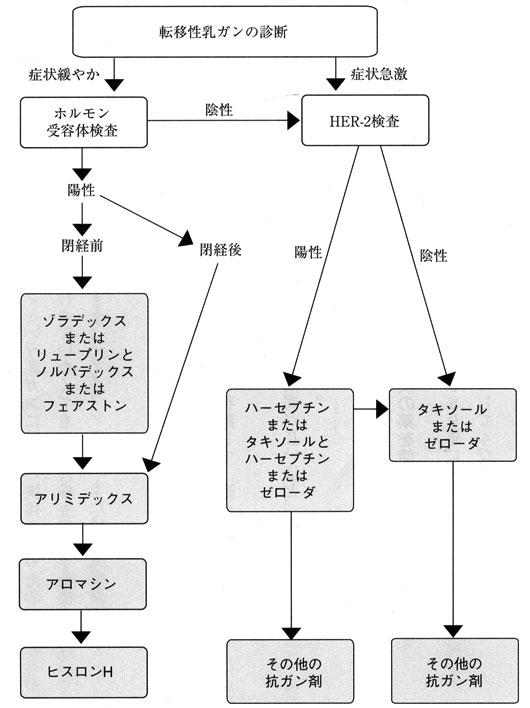

転移部位別の治療法 再発 転移に対する薬物療法 専門医が解説する

乳がんが脳転移した時の生存率 症状 治療法について解説する がん

乳がんが脳転移した時の生存率 症状 治療法について解説する がん